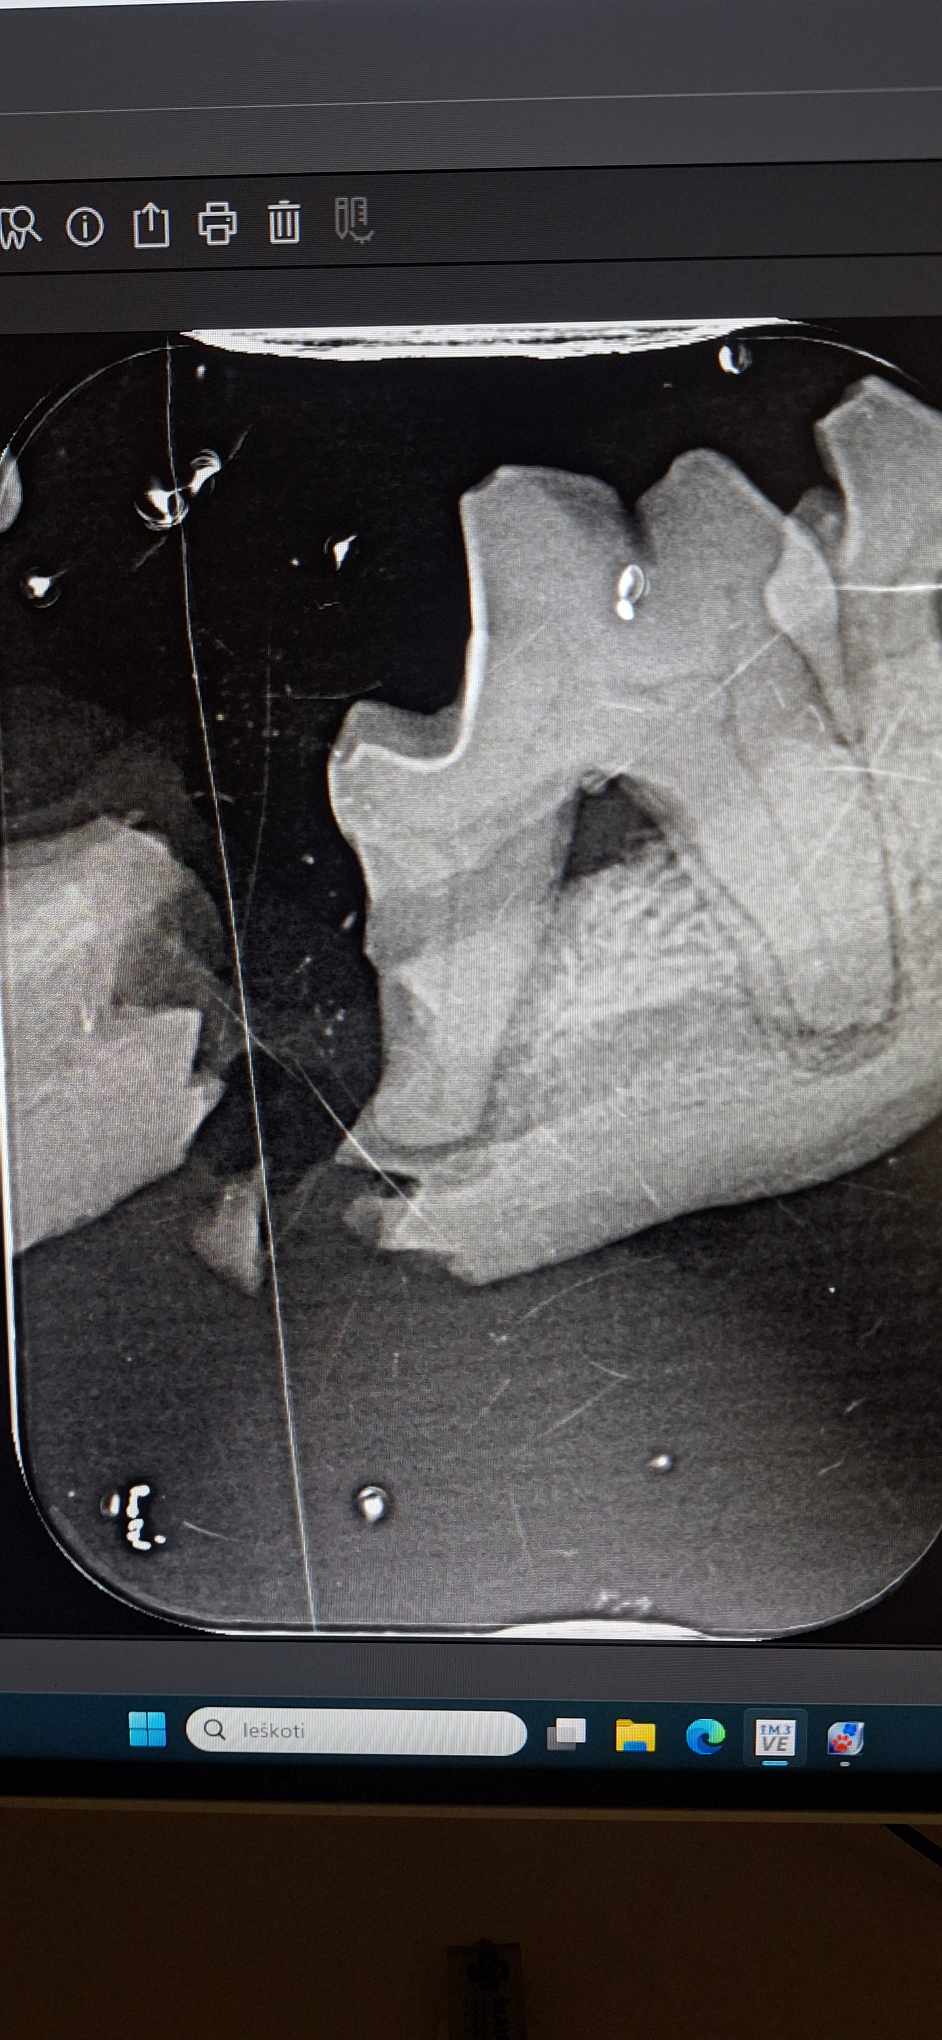

Rentgenas parodė ne tik perlūžusį bei sutrupintą žandikaulį, bet ir pakaušyje įstrigusį šratą, kurio įėjimo anga dar kraujavo… Kažkas šovė į seną mažą šuniuką, kas, galimai, turėjo įtakos įvykusiai nelaimei… Kam užkliuvo, kas toks beširdis?!

Sutvirtintas žandikaulis- ne paskutinė operacija. Dar, kai sugis, teks iš sutrupėjusios apatinio žandikaulio dalies ištraukti dantų šaknų nuolaužas.